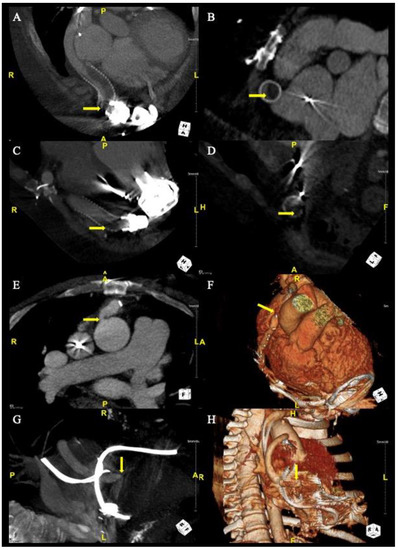

Our series demonstrates that no single symptom, laboratory result, or echocardiographic parameter is fully reliable for the diagnosis of an outflow graft obstruction. A patient may present with low flow alarms but may be otherwise asymptomatic with stable lab values. Given that some patients are asymptomatic, we are likely underestimating the true prevalence of outflow graft obstructions in the VAD population or possibly diagnosing the condition late in severe cases. The results raise the importance of awareness and urge practitioners to have a higher index of suspicion for outflow graft obstructions when patients present with non-specific symptoms not otherwise explained. CTA is a pivotal noninvasive diagnostic test that can both make the diagnosis as well as elucidate the etiology of an outflow graft obstruction (Figure 2). Decisions on management are best made in a multidisciplinary team of heart failure cardiology, non-invasive cardiology, interventional cardiology, and cardiothoracic surgery teams. The use of fenestrated bend relief may be an important preventative strategy but awaits additional studies to validate its utility [22].

Figure 2.

Algorithm for the evaluation of LVAD outflow graft obstruction. AV, aortic valve; CTA, computed tomography with angiography; HF, heart failure; IV, intravenous; MR, mitral regurgitation; RHC, right heart catheterization; TTE, transthoracic echocardiogram.